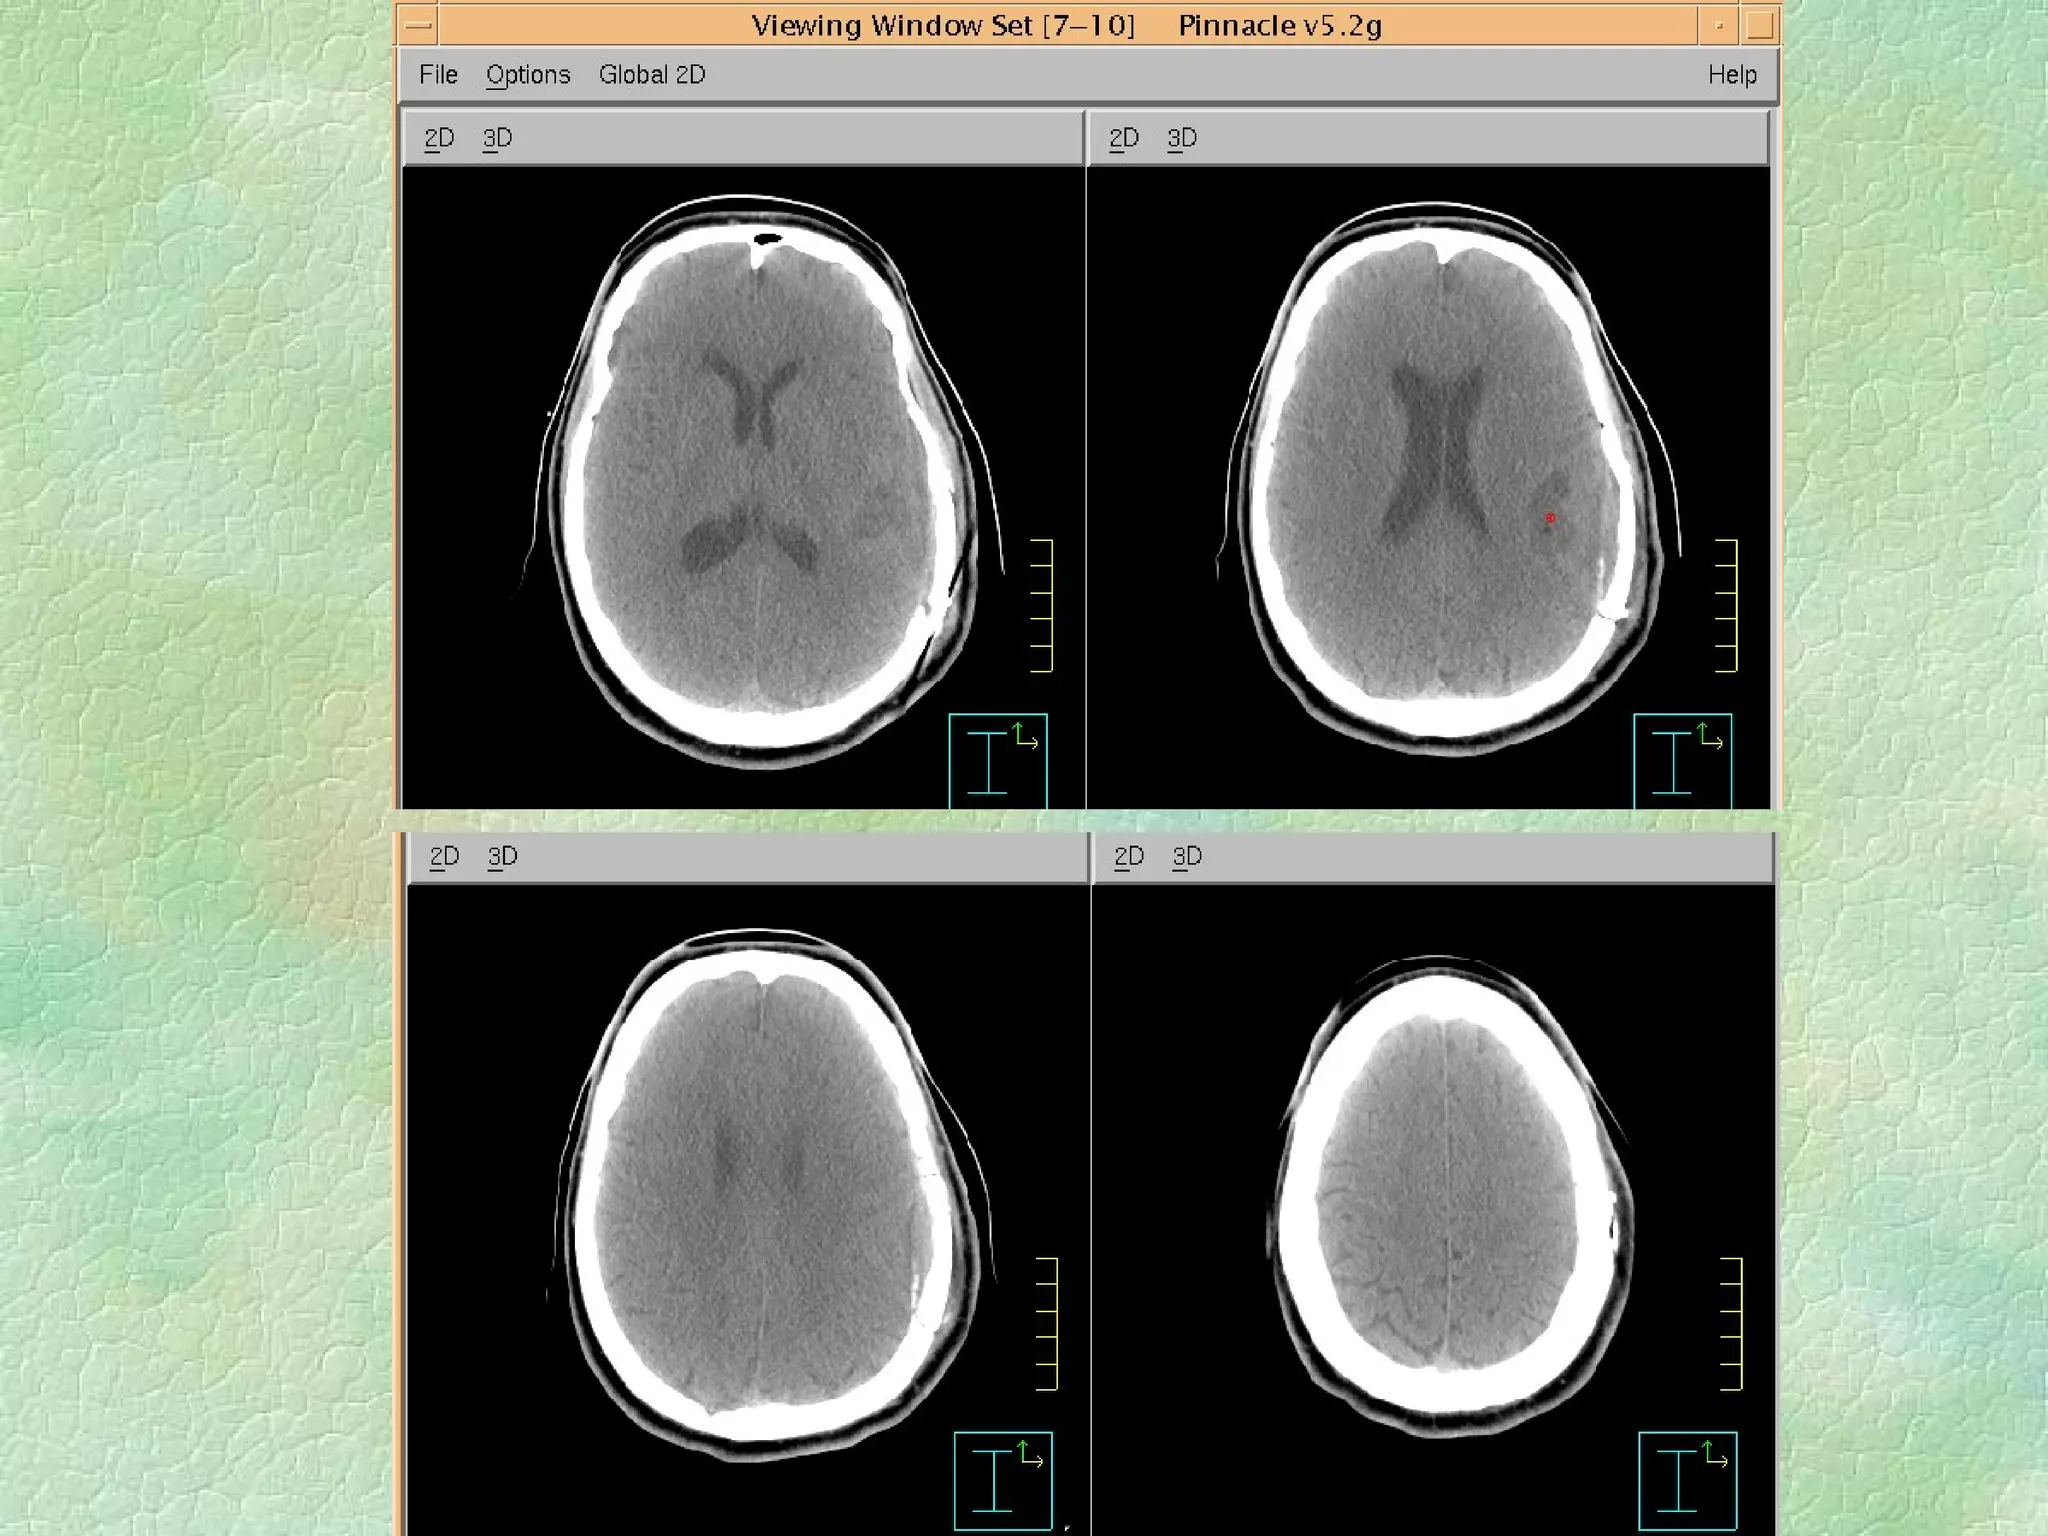

Volume Definition:  Imaging Modalities CT, US, MRI, PET, Nuc Med, Spect fMRI, Optical?, …….. Addition of margins

Virtual Simulation: -  Immobilization CT Coordinate system Structure Delineation Isocentre localization Beam placement/definition

Problems: Images are static and organ motion is not evident Correlation of imager/patient/treatment coordinate systems is non-trivial - DRRs Resolution of data set is limited by slice thickness - structure definition/DRR Imaging modality - image fusion

Problems: Images arestatic and organ motion is not evident Correlation of imager/patient/treatment coordinate systems is non-trivial - DRRs Resolution of data set is limited by slice thickness - structure definition/DRR Imaging modality - image fusion